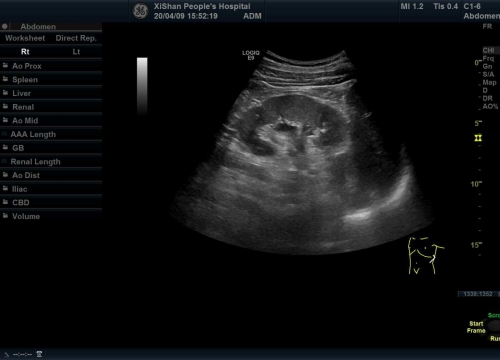

几年前,黄大爷因左肾部位酸痛曾在多家医院就诊,检查发现他左肾有一大小5.6cm左右的囊肿,外科医生建议手术切除。黄大爷害怕手术,拒绝了外科手术的建议,当他听说我院超声医学科开展硬化治疗,疗效明显,慕名而来。去年11月,黄大爷因左腰部酸痛不适前来我院就诊,彩色超声检查发现他左肾近肾门处囊肿大小为7.1*5.4cm,已压迫左肾集合系统,引起少量肾脏积水。在仔细询问病史后,超声科阚晓纯主任决定开展超声引导下肾囊肿穿刺硬化治疗术。

在全程实时的彩色超声引导下,穿刺针准确穿入囊肿内抽吸囊液,取5ml囊液行蛋白试验阳性后,抽出囊液共110ml。囊液基本抽尽后,注入硬化剂聚桂醇保留在囊内,保持持久硬化,防止囊肿复发。术后观察半小时,患者无不适,复查超声穿刺周围无出血、渗液,手术顺利完成。